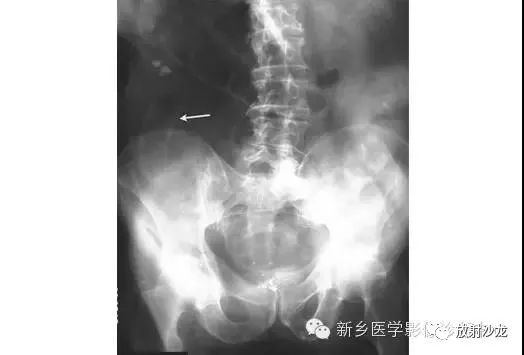

急性腹痛、便血的65岁男子行腹部平片检查所上图示。除了近端小肠梗阻,箭头指向有没有其它重大异常?

箭头指向缺血性结肠炎患者的拇指纹。拇指纹是粘膜水肿的非特异性的表现,其可见于炎性肠病、伪膜性结肠炎或缺血性肠病。随着水肿加重,结肠袋可能完全消失,留下一个管状的外观。肠道的收缩狭窄可能是其它常见的发现。